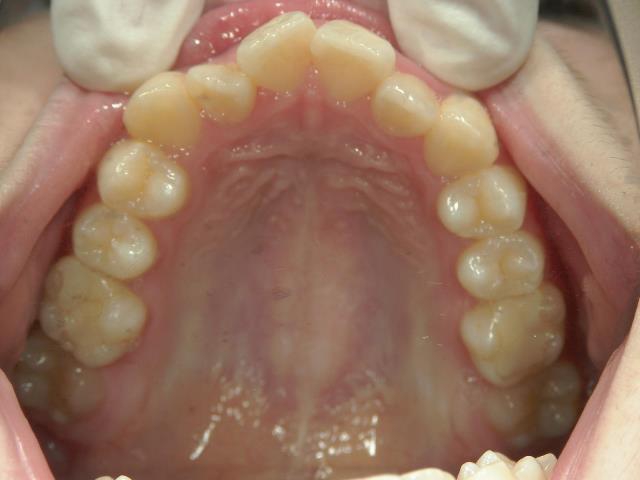

矯正歯科 治療前

矯正歯科 治療前 上顎